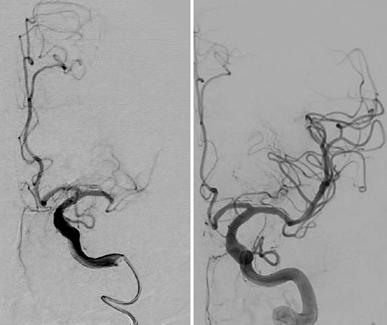

A pioneering stroke treatment at Nottingham University Hospitals NHS Trust (NUH) is now available around the clock — a move that doctors say will help save hundreds more lives each year and prevent countless others from suffering life-long disability.

The Mechanical Thrombectomy service, delivered at the Queen’s Medical Centre (QMC), provides urgent, highly specialised treatment for patients who have suffered a severe stroke caused by a blockage in one of the main arteries of the brain. The procedure involves inserting a thin tube into the artery, usually through the groin, and carefully removing the blood clot that is cutting off the brain’s oxygen supply.

Although suitable for only around 5–10% of stroke patients, the results can be remarkable. For every three to four people who undergo the procedure, one will avoid the kind of long-term disability that would otherwise change their life forever.

The 24/7 expansion means that the treatment — which had previously only been available during daytime hours — can now be offered at any time of the day or night. This is a crucial step, as the sooner the blood flow is restored, the greater the chances of survival and recovery. In stroke care, every minute counts.

Now, following a £13.5 million investment — primarily focused on radiology upgrades, specialist imaging equipment and the expansion of staff training — NUH is able to deliver the service round the clock. This investment reflects a broader national ambition within the NHS to improve access to thrombectomy procedures across England.

The extension to 24-hour availability means hundreds more patients every year will have access to the treatment, which can make the difference between a full recovery and a lifetime of dependency.